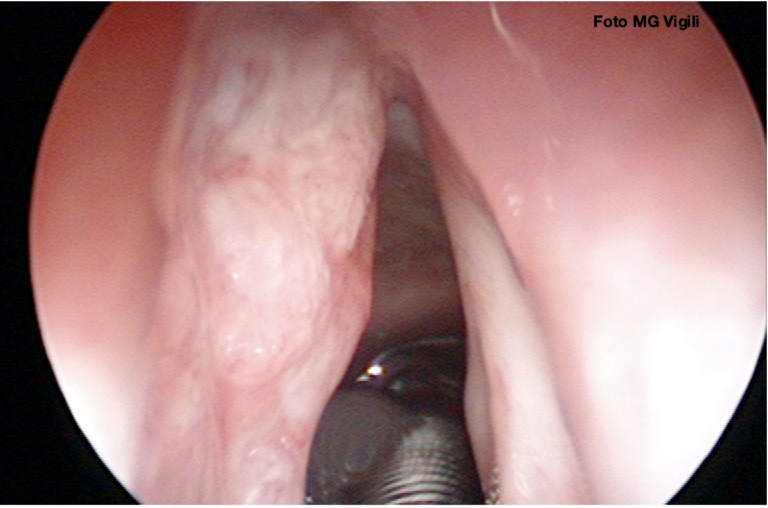

Valore della profondità di invasione tumorale (DOI) nei tumori laringei glottici

Profondita’ di invasione (DOI) nel tumore della lingua: valutazione clinica e tecniche di imaging

Accuratezza della RM nella determinazione della profondità di invasione (DOI) nei tumori della bocca